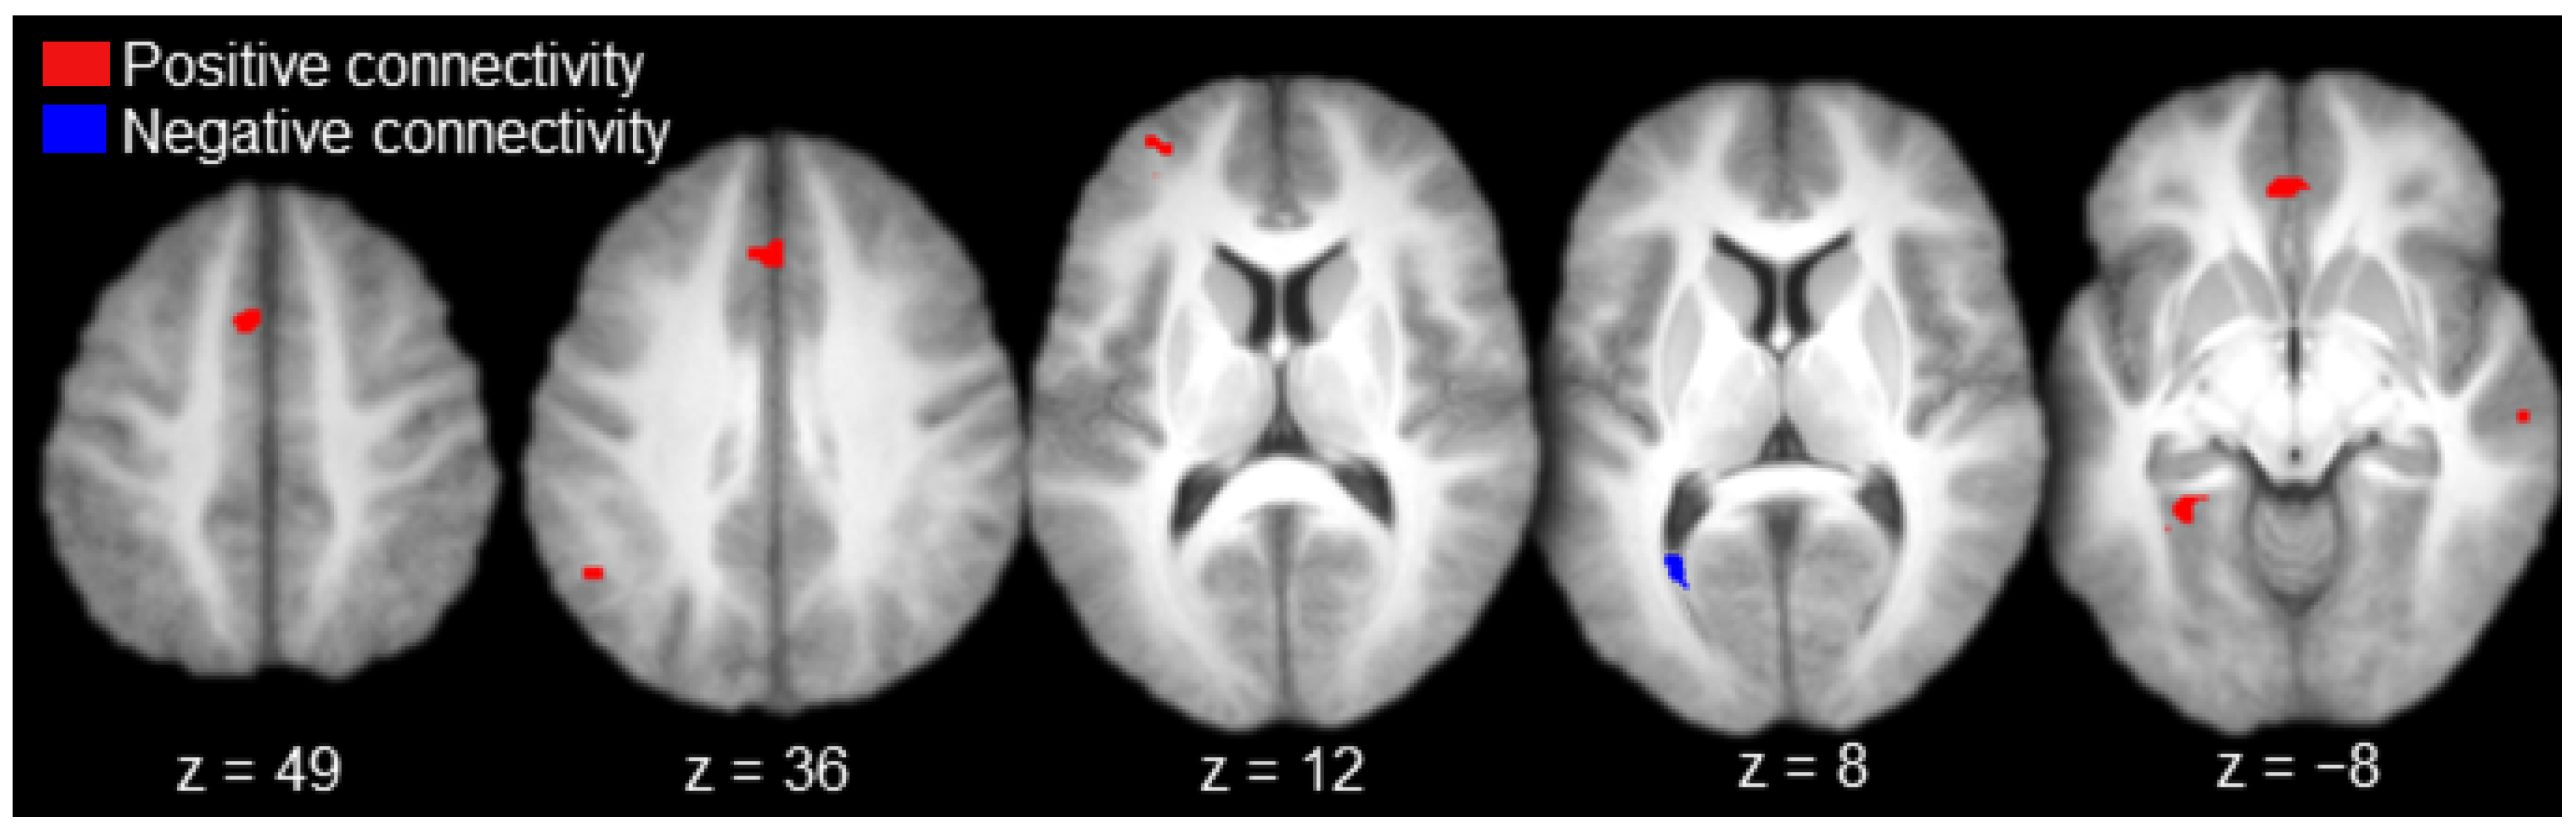

| All participants | |||||

| Positive activations | |||||

| L. Anterior Prefrontal Cortex | 10 | −32 | 51 | 12 | 31 |

| L. Medial Prefrontal Cortex | 6 | −5 | 11 | 48 | 50 |

| Bilateral Anterior Cingulate Gyrus | 32 | 0 | 24 | 38 | 30 |

| Bilateral Anterior Cingulate Gyrus | 32 | 0 | 39 | −10 | 32 |

| L. Angular Gyrus | 39 | −44 | −54 | 34 | 51 |

| R. Superior Temporal Sulcus | 21/22 | 60 | −21 | −7 | 29 |

| L. Parahippocampal Cortex | 19/37 | −27 | −46 | −-7 | 27 |

| Negative activations | |||||

| L. Calcarine Sulcus | 17 | −26 | −62 | 8 | 30 |